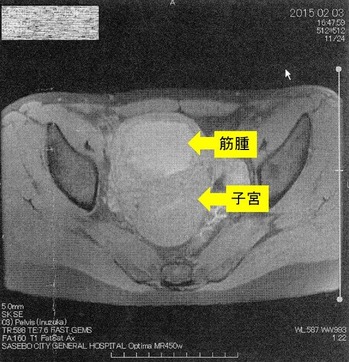

´ÁÊýÌô¤Ç»ÒµÜ¶Ú¼ð9Ѥ¬7ѤËÀ¸ÍýÄˤâ¿Î̽зì¤â²þÁ±¼ê½Ñ²óÈò¤Ç¤¹¡£¶Ú¼ð¤ÎMRI¼Ì¿¿¤Ç¤¹

¡Ú2015ǯ2·î3Æü¡¡£Í£Ò£É¼Ì¿¿¡Û

¢¨Çò¤¤Éôʬ¤¬¶Ú¼ð¡¢¼þ¤ê¤ÎÉôʬ¤¬»ÒµÜ¤Ç¤¹¡£